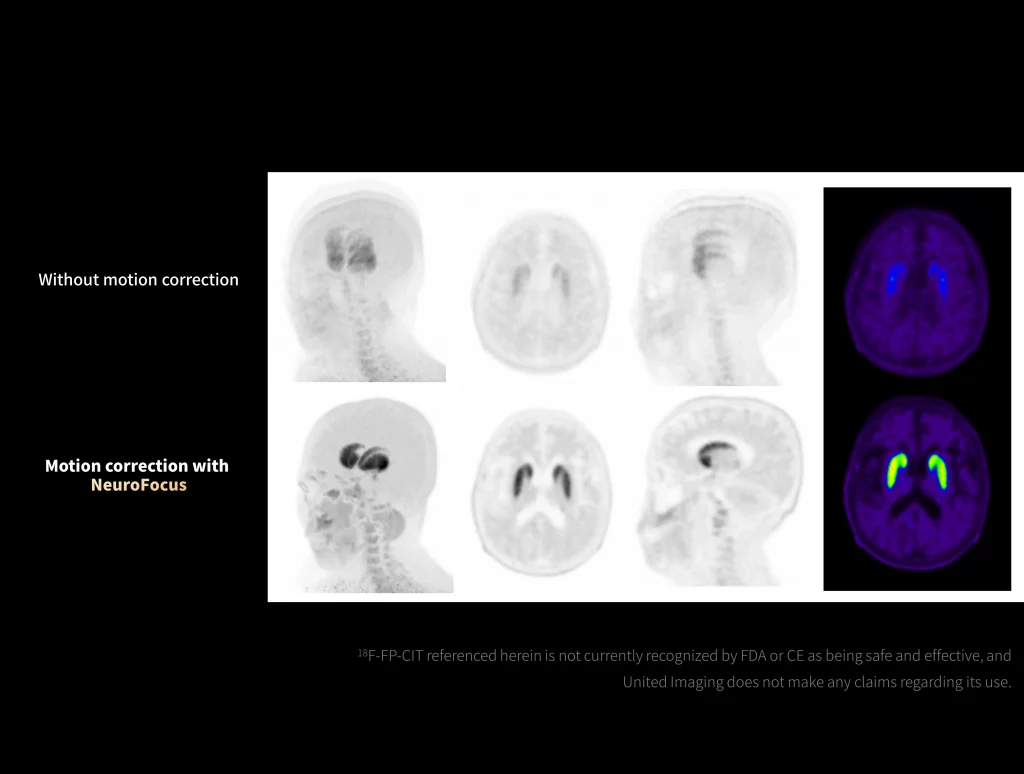

uMI Panorama is greatly empowered by innovative technologies integrated into the uExcel SCAN and uExcel CARE workflows. With uExcel SCAN, you can rely on intelligent positioning, scanning, and motion correction to streamline your routine tasks and maximinze your work efficiency. And uExcel CARE features uExcel DPR and uExcel AIIR reconstruction algorithms to ensure clear images even at low doses.

With the ultra-high system performance, uMI Panorama faces up to the challenges of tracers with different half lives and the complex scanning conditions, without compromise for image quality.

New-Tracer Imaging

Click on different tracers to see the images.